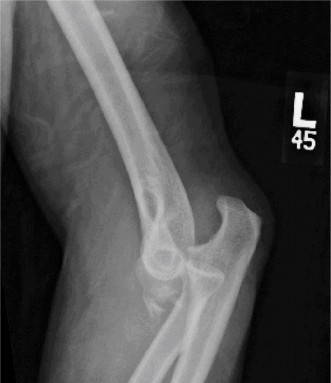

It should be noted that reverse total shoulder arthroplasty is also the procedure of choice in patients with cuff-tear arthropathy (aka rotator cuff arthropathy). Characteristics of cuff-tear arthropathy include superior migration of the humerus due to a massive rotator cuff tear, glenohumeral joint destruction, subchondral osteoporosis, and humeral head collapse (see Fig. 2–17). A reverse total shoulder

Figure 2–17_X-rays of a patient showing evidence of cuff tear arthropathy. The humerus is migrated superiorly, the glenohumeral joint is destroyed, there is subchondral osteoporosis, and the humeral head is collapsed. (From Ecklund KJ, Lee TQ, Tibone J, Gupta R. Rotator cuff tear arthropathy. _J Am Acad Orthop Surg. 2007;15(6):340–349.)